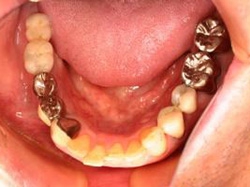

両側5歯症例

両側5歯症例両側5歯症例両側5歯症例 主訴-義歯のバネが壊れて手前の歯が痛んできた。 術前(旧義歯装着、鏡像) 術前(下顎粘膜面、鏡像)術前(下顎粘膜面、鏡像)術前(下顎粘膜面、鏡像) 術前レントゲン術前レントゲン術前レントゲン 術前口腔内(正面観)術前口腔内(正面観)術前口腔内(正面観)

術後(鏡像)術後(鏡像)術後(鏡像) 術後口腔内(正面観)術後口腔内(正面観)術後口腔内(正面観)もう入れ歯は要らなくなりました。 術後レントゲン術後レントゲン術後レントゲン